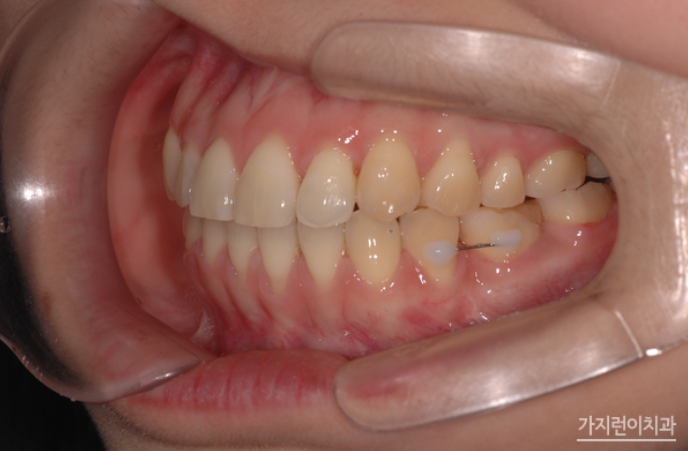

해당 환자분의 경우는 사랑니를 어금니로 대체하는 교정을 계획했었는데요. 위 사진을 보면 사랑니를 세우면서 임플란트를 식립하지 않고 발치 공간을 닫았습니다. 하악 좌측의 사랑니를 효과적으로 세우기 위해 modified bonded cantilever (MBC) spring을 사용했는데요.

상하악 중심선도 잘 맞추었고 교합도 정상교합으로 맞춘 것을 볼 수 있습니다. 하악 사랑니도 잘 세워진 것을 눈으로 확인할 수 있을 정도가 되었는데요. 더 쉽게 보기 위해 교정 전후의 엑스레이 사진도 확인해보겠습니다.